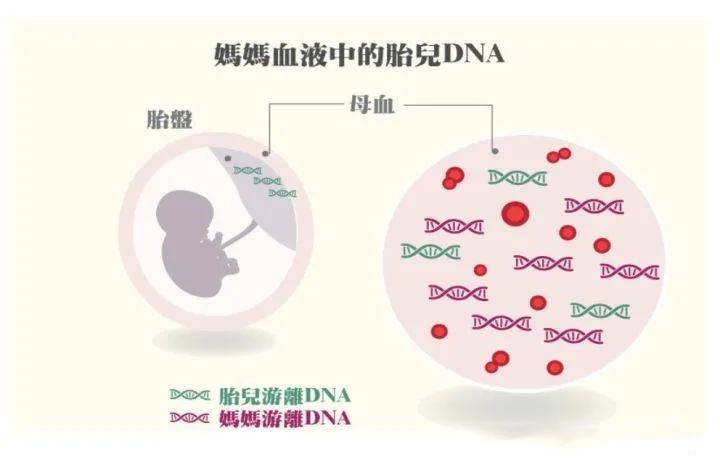

梅州哪里可以做怀孕亲子鉴定呢?无创胎儿亲子鉴定

梅州哪里可以做怀孕亲子鉴定呢?无创胎儿亲子鉴定